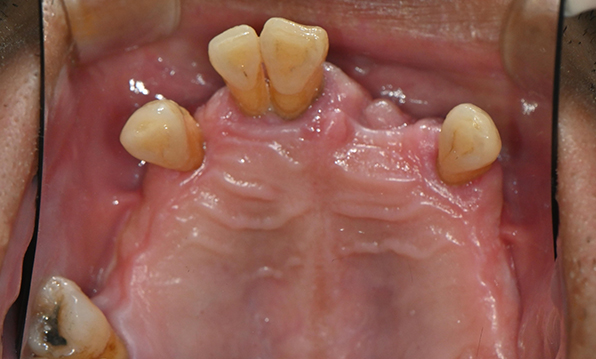

잇몸뼈가 얇은 상태

-

잇몸뼈 충분히 이식 후 임플란트 식립

성공을 위한 노하우, 잇몸뼈 재건 기술

전체 임플란트를 해야하는 환자들은

대부분 고령의 환자들로 오랜 틀니 사용

또는 노화로 인해 치조골이

거의 남아있지 않는 경우가 많습니다.

이 때, 치조골 이식을 병행하여 잇몸뼈 재건 후 안정적인 임플란트 식립을 하고 있습니다.

치료기간 : 2021.04.12~2021.09.15